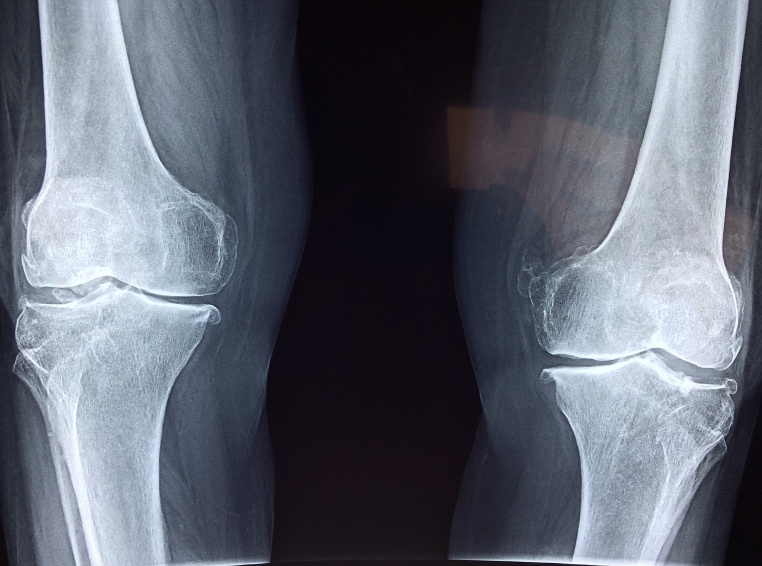

계단 오르내릴 때 무릎이 욱신거리거나, 앉았다 일어설 때 관절이 뻣뻣하다면…

단순 노화가 아니라 연골 마모가 시작된 신호일 수 있어요. 오늘은 관절 건강 관리의 핵심 성분 중

콘드로이친은 골관절염(OA)과 같은 퇴행성 질환에서 통증과 불편감을 줄이는 데 도움을 줍니다.